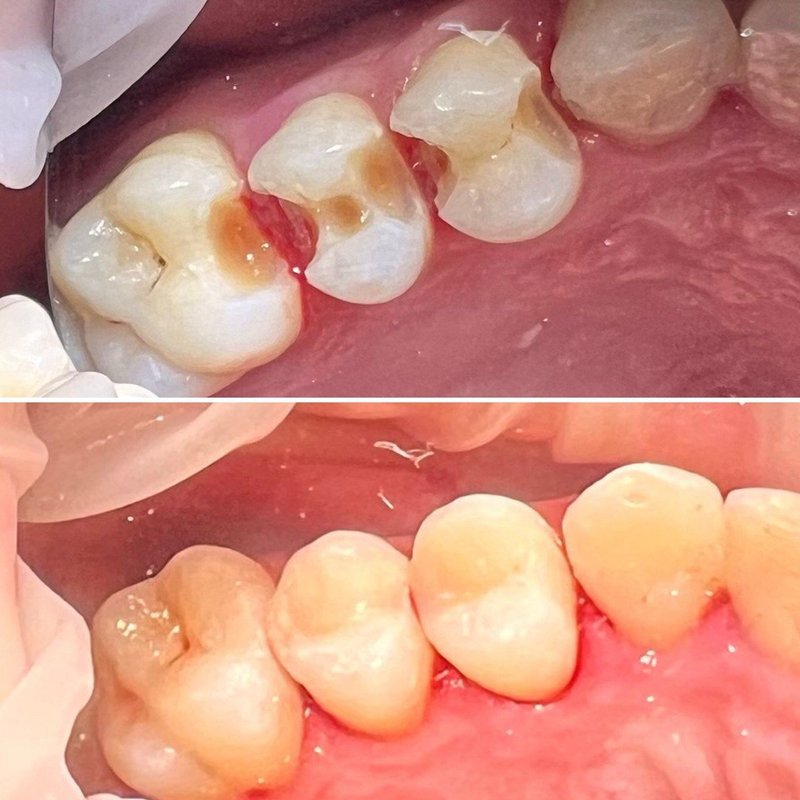

Фотогалерея